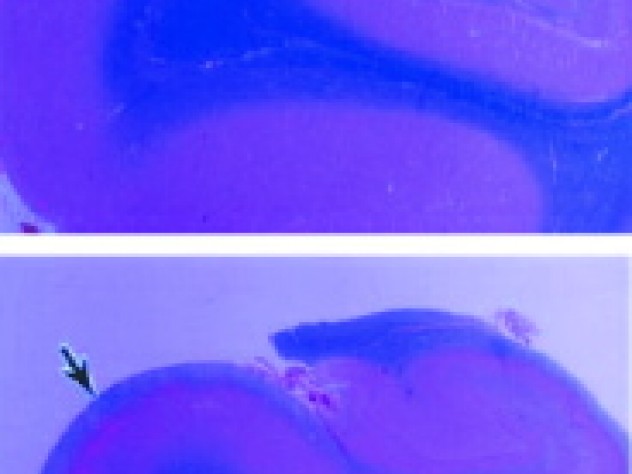

Photomicrographs of brain cross-sections show an increased amount of myelin in a 54-year-old (below) compared with a 24-year-old (above).

Myelin is the covering of nerve fibers; it both insulates them and speeds nerve conduction. The accumulation of myelin is called myelination. During child development, myelination correlates with maturing patterns of behavior. Infants, for example, lack the fine motor coordination to move an index finger independently, since their nerves are insufficiently myelinated. "As a child is beginning to walk and talk," Benes explains, "the brain is actively myelinating."

Even so, in the part of the brain where Benes was looking, the evidence was hard to overlook. Long after age five, significant increases in myelination occurred in the medial temporal lobe, a brain region responsible for emotion, memory, and the integration of the two. "I scratched my head and thought, 'That's kind of strange,'" she says. "It was an important finding that needed to be replicated."

Myelination levels kept rising into the early twenties, she found, and then flattened out after having doubled in the second decade of life. But myelination took off again in the forties and continued into the mid fifties, accumulating, on average, another increase of 50 percent before leveling off again.